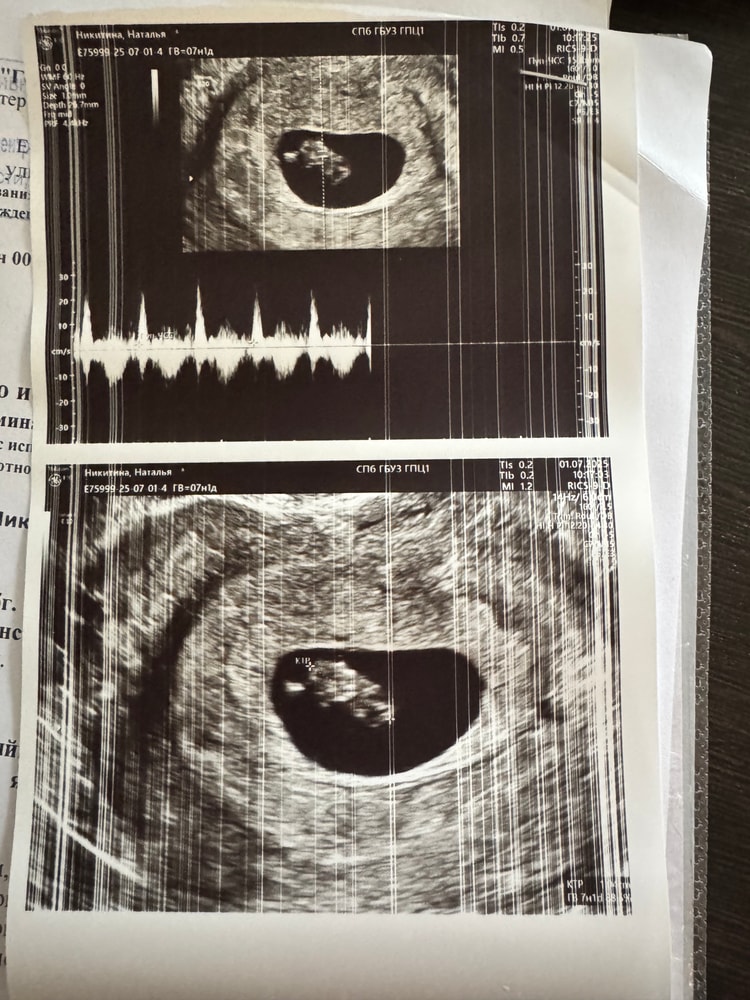

Хроники УЗИ: 7+1

УЗИСегодня было третье УЗИ! Наконец-то услышала сердечко малыша, и кажется, немного успокоилась.

Срок: 7 недель 1 день

ПЯ: 23,1 мм

КТР: 10,4 мм

ЧСС: 153 уд/мин